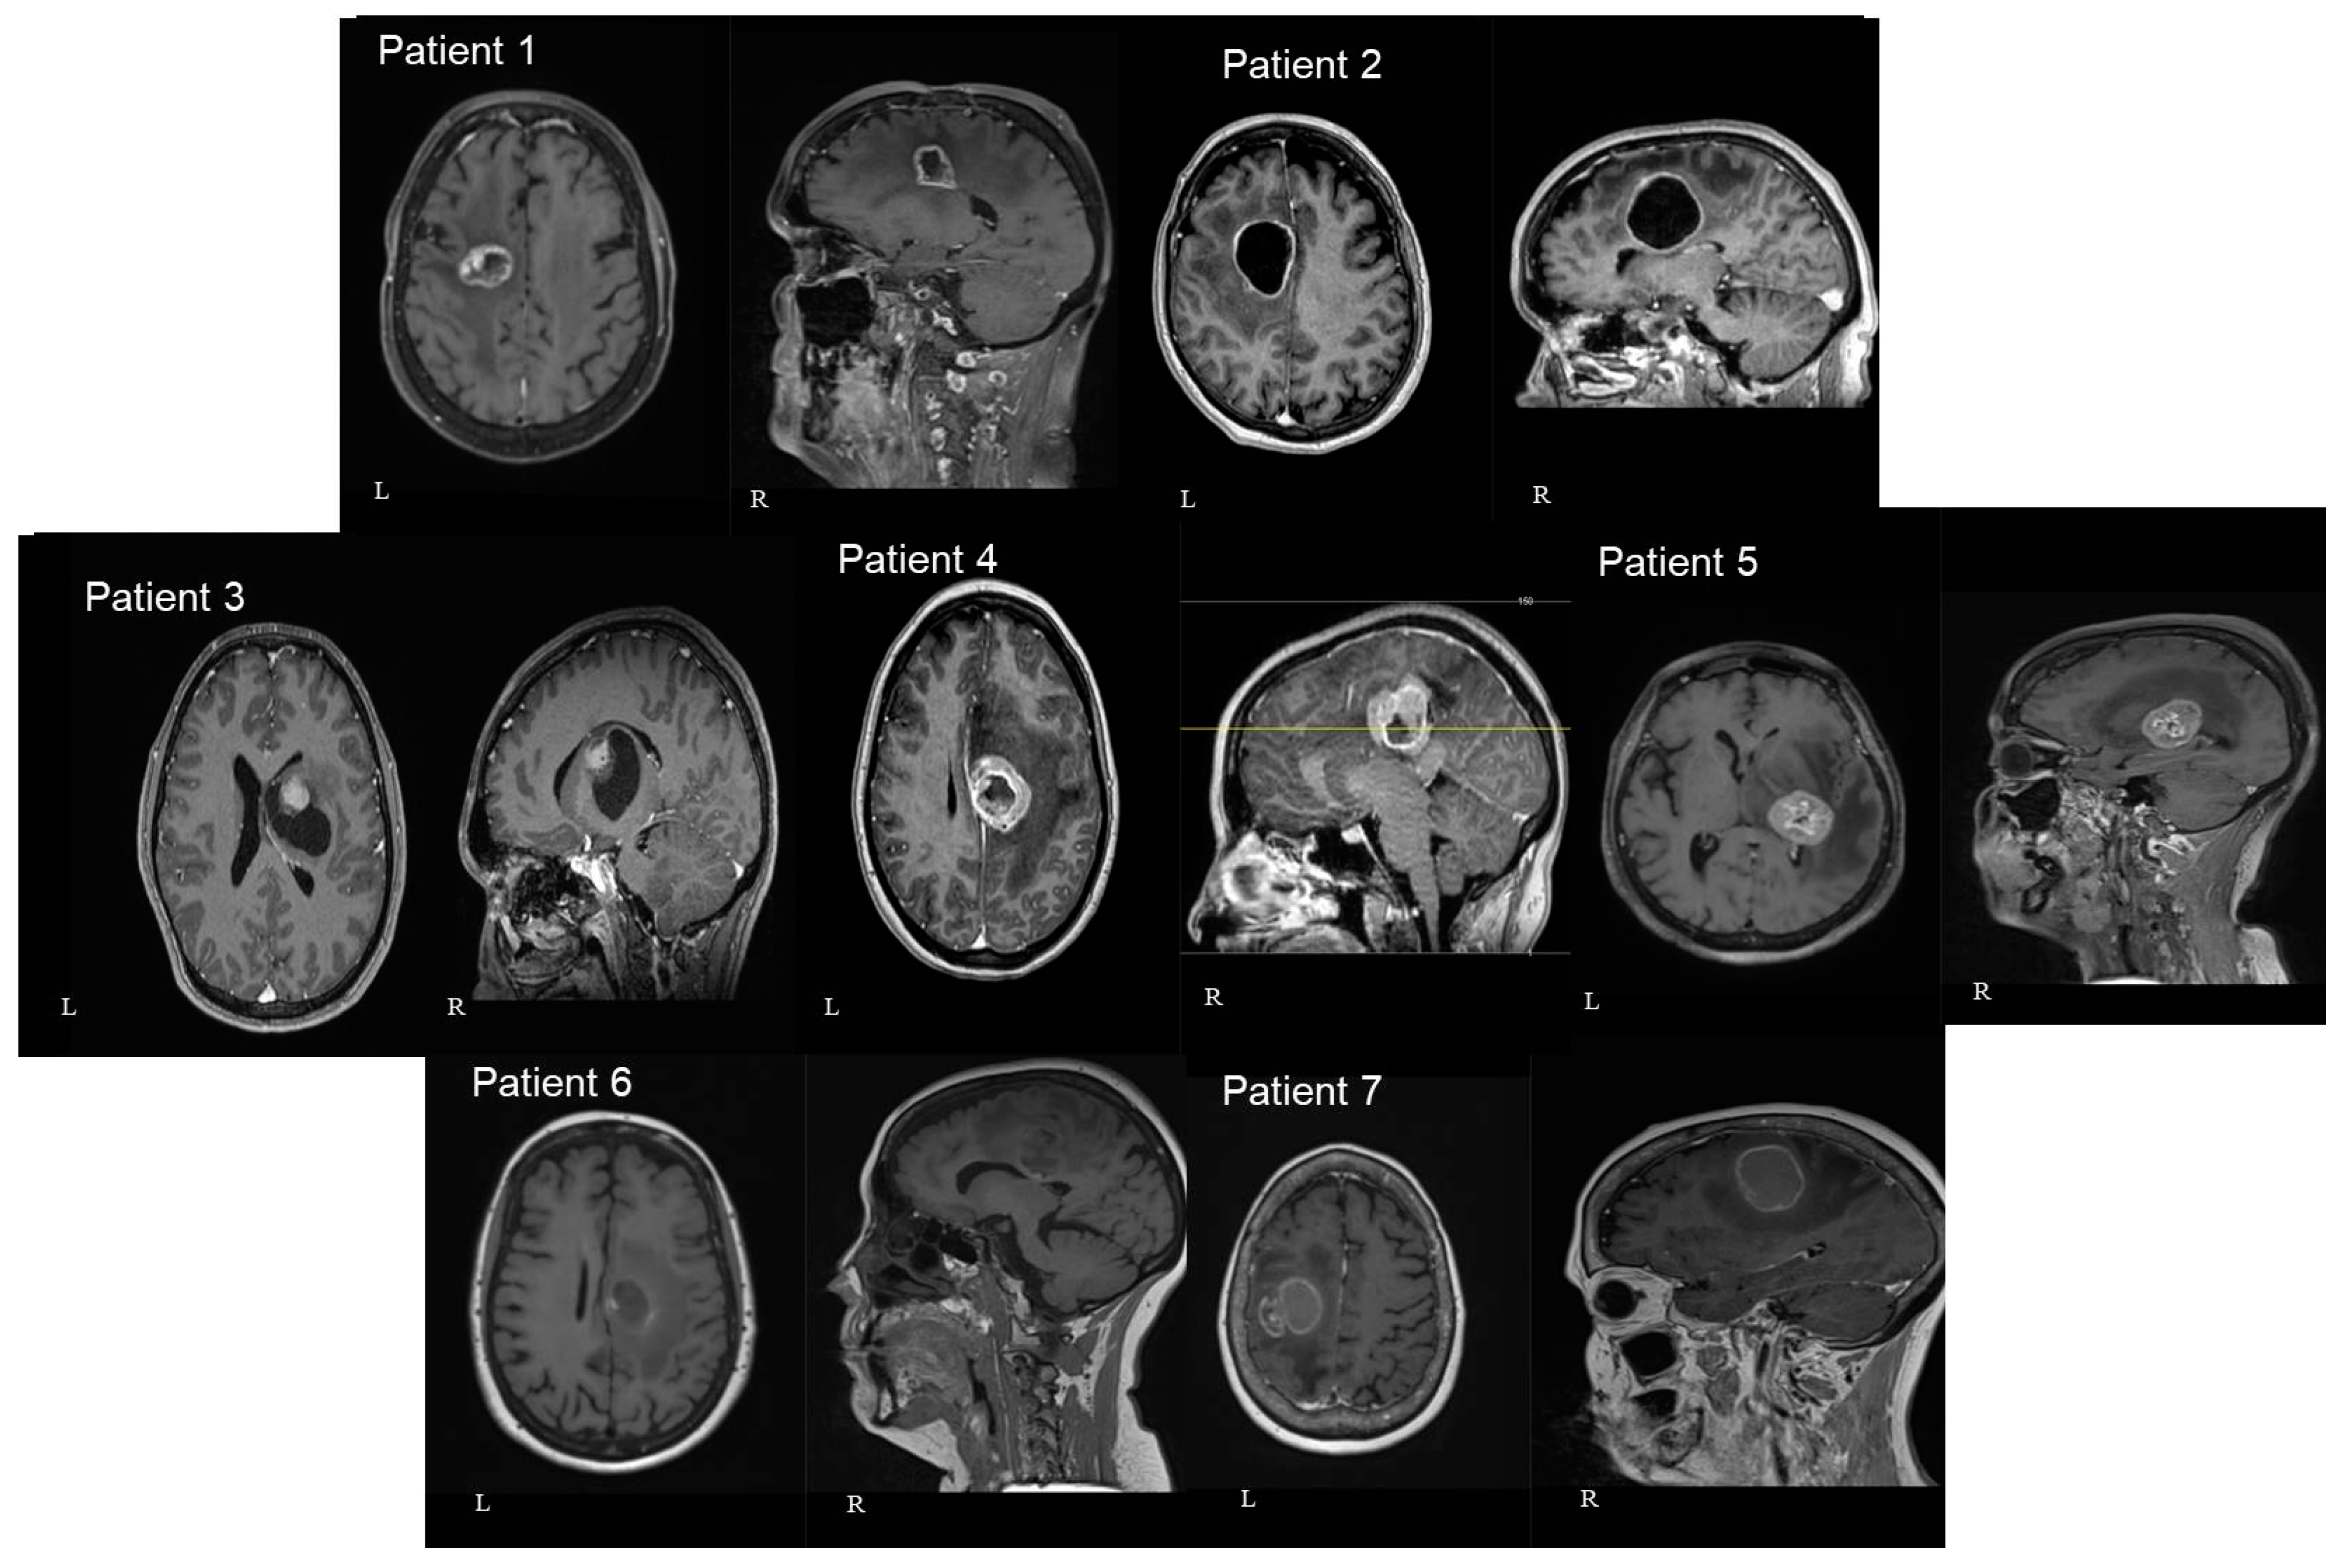

Figure 3.

Schematic representation of tumor location. Left image—patients with right-sided lesions. Right image—patients with left-sided lesions. Each number corresponds to the patient’s number in Table 1. The volume of the sphere approximates the volume of the specific lesion. Green—corticospinal tract; blue—fronto-aslant tract; orange—fronto-striatal tract.

In three patients the lesion was located at the cingulate gyrus. In two of them, the tumor was centered in the precentral gyrus, and in the final two, at the basal ganglia involving the thalamus and the internal capsule. Four patients had left-sided lesions and three had right-sided lesions. The mean distance between the lesions and the cortex as measured in the preoperative MRIs was 30.9 mm (range: 7 mm–46 mm) (Figure 3 and Figure 4). The mean volume of the included lesions was 13.2 cm3 (range: 3.3–32.6 cm3).